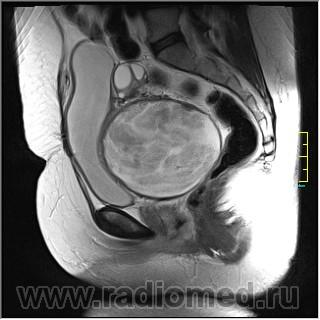

Госсипибома.

Госсипибома, или текстилома - это название группы осложнений после хирургических вмешательств в результате оставленных в теле пациента инородных предметов. Термин "Госсипибома" состоит из латинского слова gossypium (хлопок) и слова из языка суахили boma (место, где что-то спрятано), по другим данным - греческого "oma" - частицы, обозначающей опухоль. Так или иначе, госсипибома представляет собой матрикс из хлопка, окруженный гранулемой инородного тела. Термин текстилома появился позже и стал использоваться вместо термина "госсипибома", когда в хирургии вместо хлопка начали применять синтетические материалы.

Ж, 35 лет. Состояние после субтотальной гистерэктомии без придатков по поводу осложненных родов около полугода назад. Обратилась на МРТ в связи с болями и неприятными ощущениями в области малого таза.

Вот такая картинка.